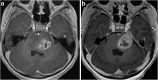

Meckel's cave is a dural recess in the posteromedial portion of the middle cranial fossa that acts as a conduit for the trigeminal nerve between the prepontine cistern and the cavernous sinus, and houses the Gasserian ganglion and proximal rootlets of the trigeminal nerve. It serves as a major pathway in perineural spread of pathologies such as head and neck neoplasms, automatically upstaging tumours, and is a key structure to assess in cases of trigeminal neuralgia. The purpose of this pictorial review is threefold: (1) to review the normal anatomy of Meckel's cave; (2) to describe imaging findings that identify disease involving Meckel's cave; (3) to present case examples of trigeminal and non-trigeminal processes affecting Meckel's cave.

Teaching points: • Meckel's cave contains the trigeminal nerve between prepontine cistern and cavernous sinus. • Assessment is essential for perineural spread of disease and trigeminal neuralgia. • Key imaging: neural enhancement, enlargement, perineural fat/CSF effacement, skull base foraminal changes.